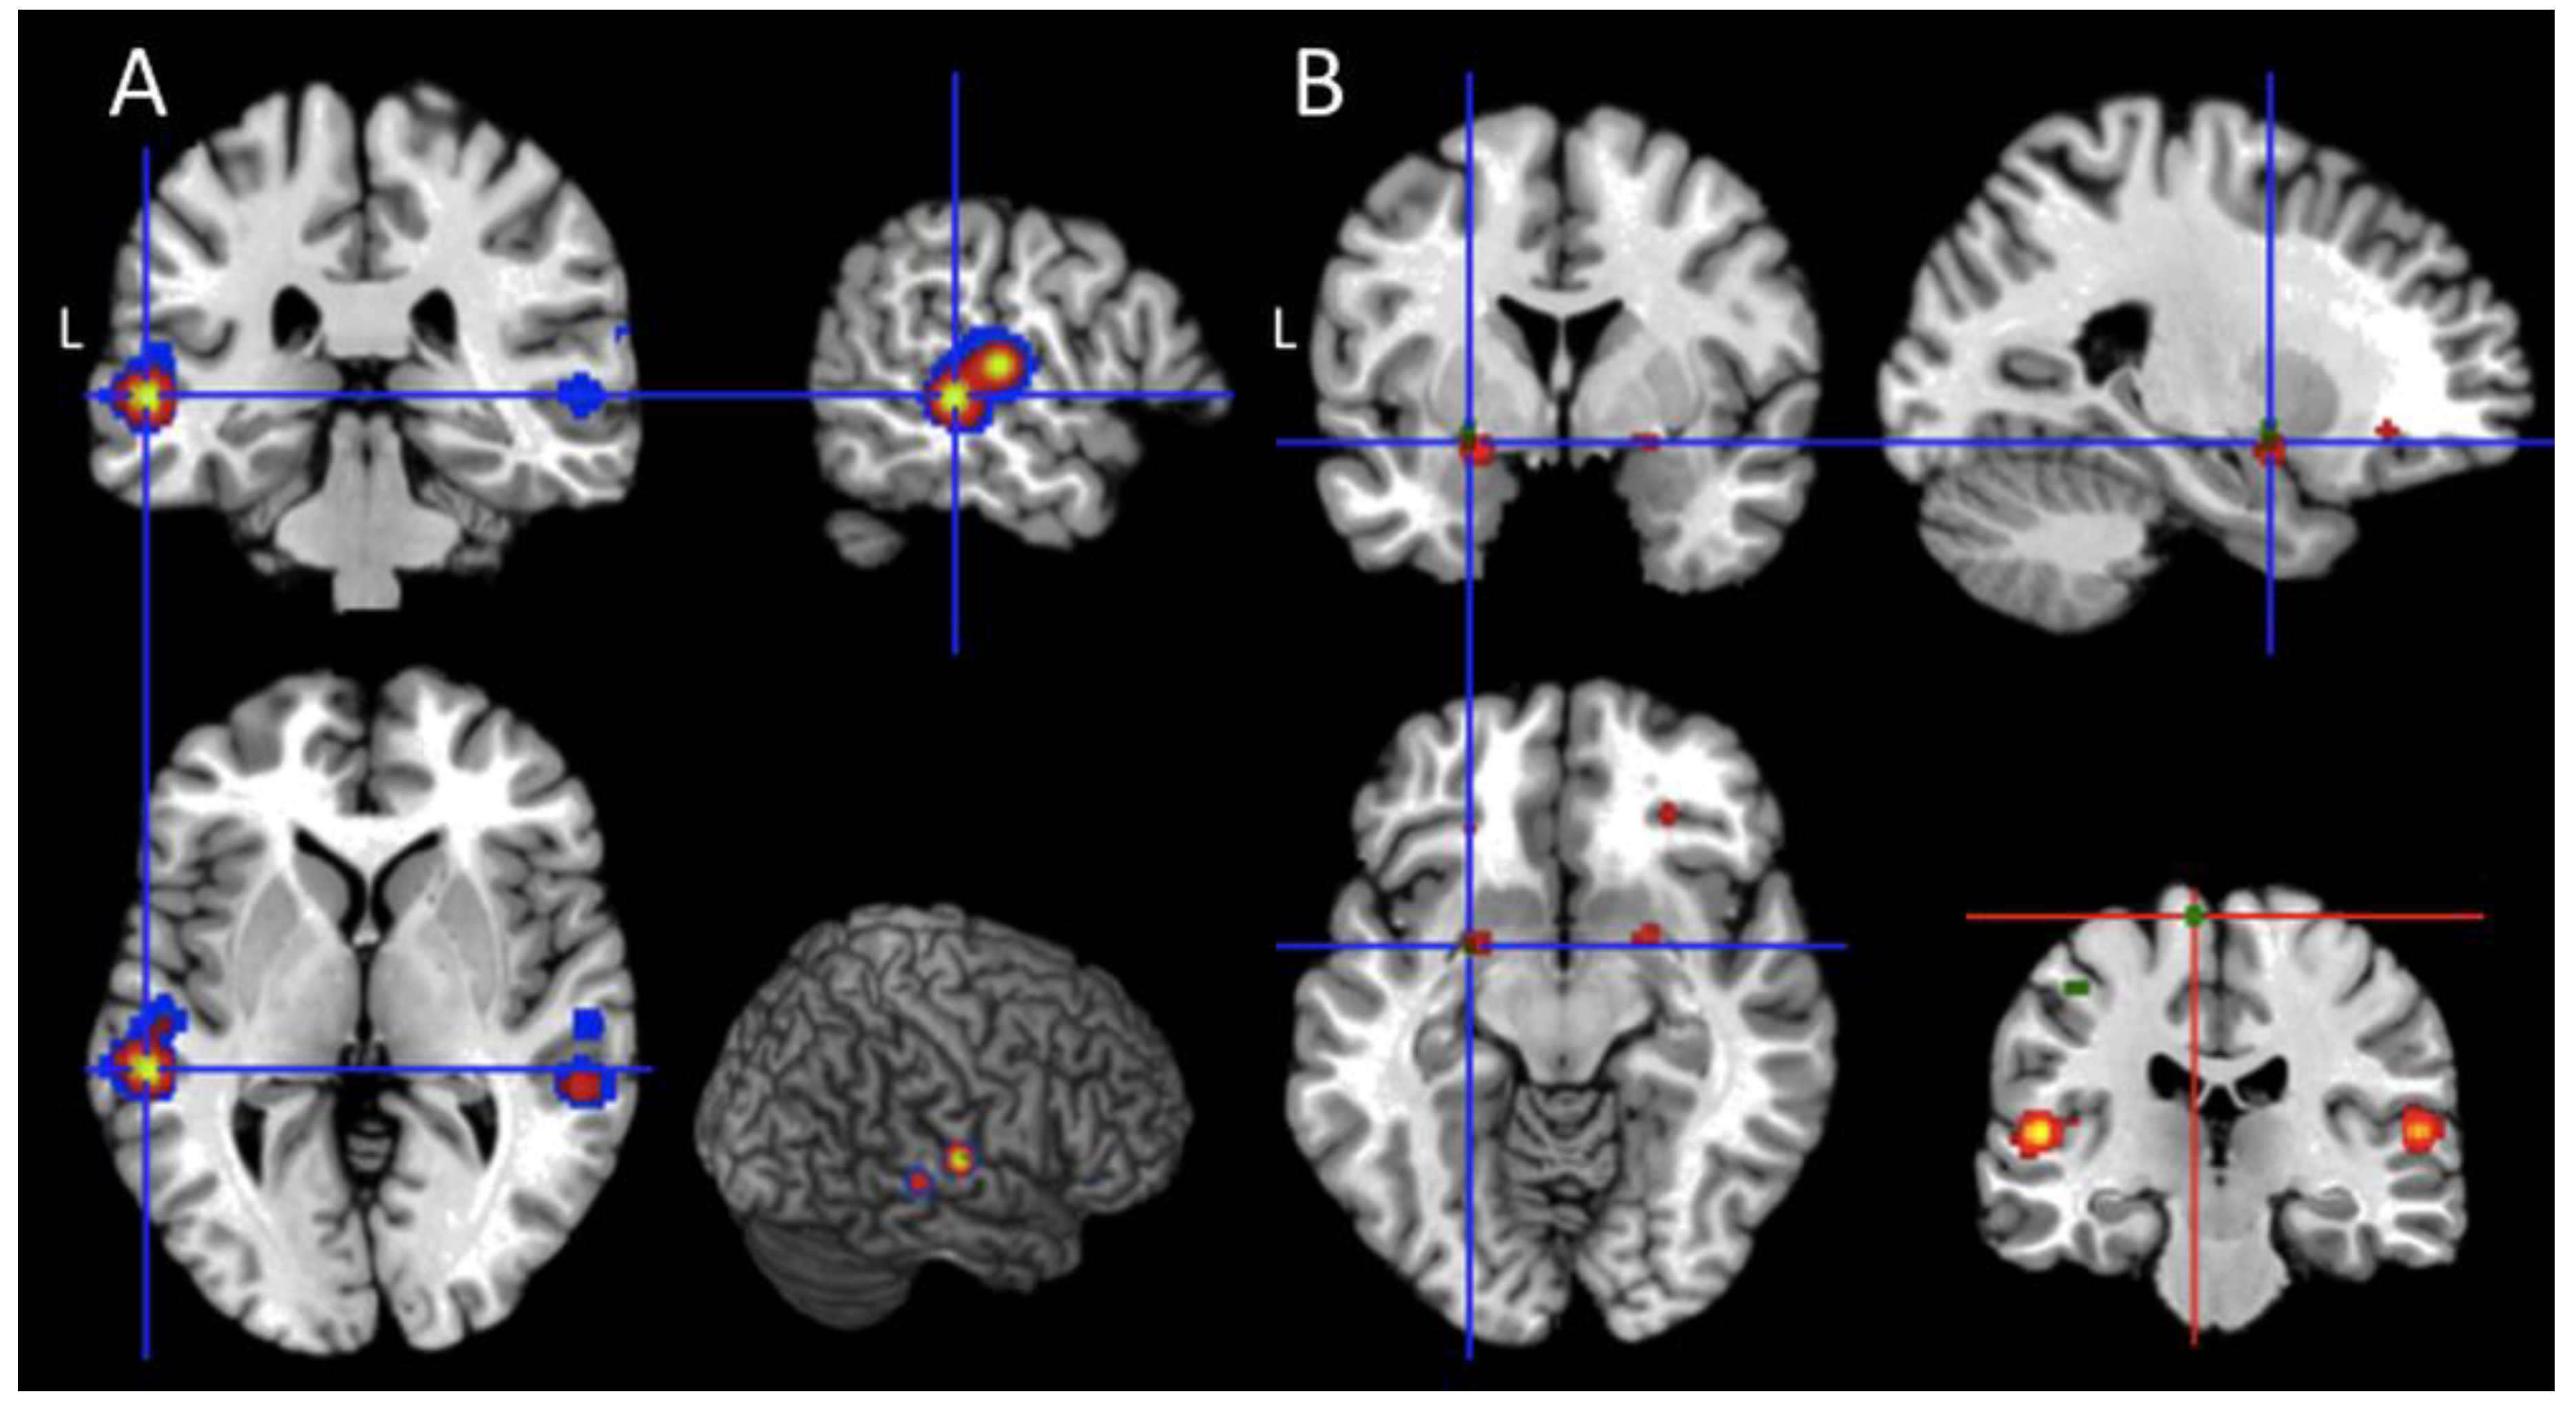

- Passive Task (Table 4): from the set of passive task activation peaks, we found a significant effect in the orbital cortices (BA 47) and in the inferior frontal gyri (pars triangularis; BAs 46, 45), at the border with the middle frontal gyrus (BA 9), in the lateral temporal cortices as well in subcortical regions. In particular, the two subcortical clusters were located (i) between the amygdala, the globus pallidus on the right hemisphere, and (ii) between the amygdala and the parahippocampal gyrus of the left hemisphere;

- Active Task (Table 4): from the pool of active task-related foci, significant clusters were found in the paracentral lobule (BAs 4 and 6), in the inferior parietal lobule (BA 40), in the fusiform gyrus (BA 20), in the lingual gyrus (BA 19), in the middle occipital gyrus (BA 19), in the superior occipital gyrus (BA 18), and in the cuneus (BA 18) of both hemispheres. Concerning the left hemisphere, we found a significant effect in the superior frontal gyrus (BA 8), in the inferior frontal gyrus pars triangularis (at the border with the middle frontal gyrus; BA 9), in the postcentral gyrus (BA 2), and in a left subcortical cluster located between the amygdala and the putamen nucleus. Moreover, we found a significant effect in the right middle frontal gyrus (BAs 8, 9, and 10);

- Passive and Active task - conjunction and contrast analysis: the active and passive map (Table 5) was computed to explicitly test hypothesis 1. As clearly reported in Table 5, the only brain region commonly activated by active and passive paradigm is the subcortical cluster located between the left amygdala and the putamen. Finally, the contrast analyses (p < 0.001 uncorrected) revealed a higher level of activation for the comparison “active > passive tasks” in the left paracentral lobule (x = −6, y = −24, z = 68; BA 6); the reversed contrast, namely “passive > active tasks” did not show any significant effect;

- Unresponsive Wakefulness Syndrome (UWS; Table 4): the patients in UWS showed significant activations in the inferior frontal gyrus, both in the pars orbitalis (BA 47) and in the pars triangularis (45, and 46) extending to the border with the middle frontal gyrus (BA 9), in the supplementary motor area (SMA; BA 6), in the lateral temporal cortices, and the amygdala (BA 34) of both hemispheres. Furthermore, a significant effect was found at the subcortical level between the amygdala, the globus pallidus on the right hemisphere and between the amygdala and the parahippocampal gyrus of the left hemisphere;

- Minimally Conscious State (MCS; Table 4): we found significant clusters of activations in the orbital part of the inferior frontal gyrus (BA 47), in the lateral temporal cortices, and in the fusiform gyrus (BA 20) of both hemispheres. Also, in this case, a significant effect was found at the subcortical level between the amygdala, the globus pallidus on the right hemisphere and between the amygdala and the parahippocampal gyrus of the left hemisphere. Furthermore, significant results emerged in the left inferior frontal gyrus at the border with the middle frontal gyrus (pars triangularis; BAs 9 and 45);

- UWS and MCS patients—conjunction and contrast analysis: the activations described across studies and shared by the two classes of patients were located in the orbital portions of the inferior frontal gyrus (BA 47), in the superior temporal gyrus (BA 41), and in the two subcortical clusters located around the amygdala of both hemispheres (Table 5). Furthermore, significant shared activations were found in the dorsal part of the left inferior frontal gyrus (at the border with the middle frontal gyrus; BAs 9 and 45), in the left middle temporal gyrus (BA 22), and in the right heschl gyrus (at the border with the insular cortex; BA 13). The between-groups contrast analyses did not show any significant result.